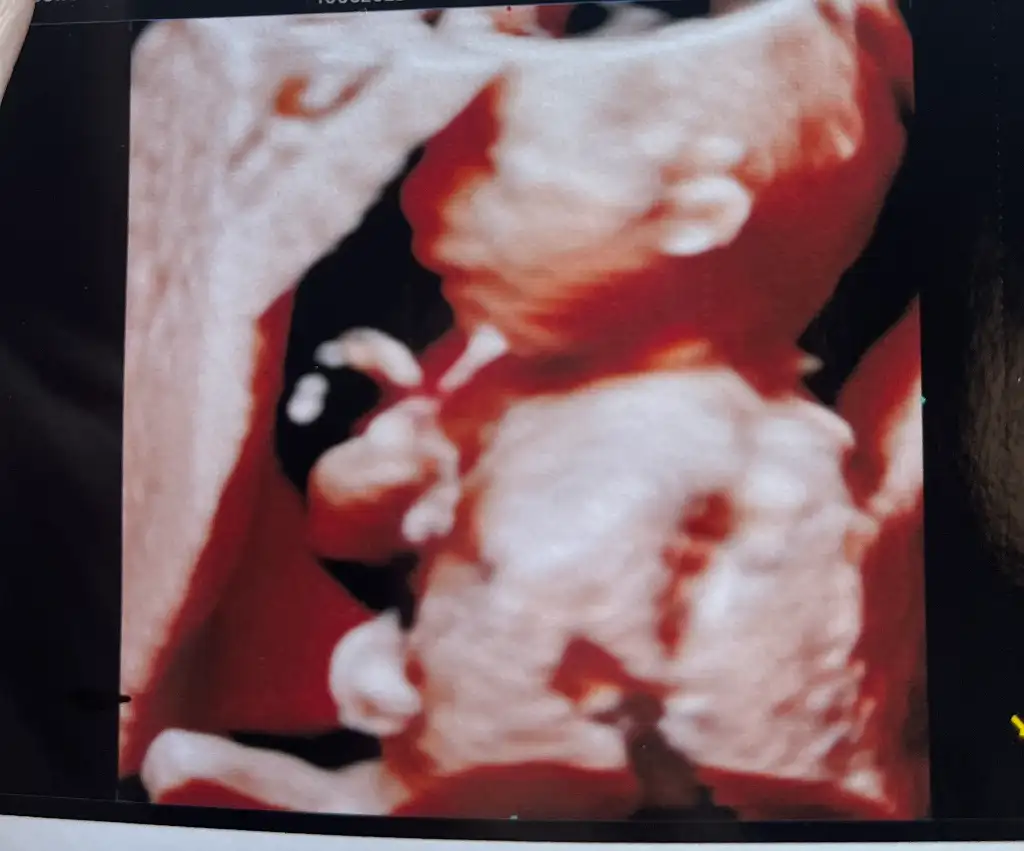

Aman maşallah güzelliğe bak allah nazarlardan korusun inşallahh. Sen 2 hafta sonra detaylıya gidince kaç haftalık olacaksın canım?Kızlar nasılsınız benim minnoşum bugün zorda olsa poz verdi elini hep yüzüne koyuyor. Biraz rahatsız etti doktor amcası. 2 hafta sonraya da detaylıya randevu aldım.

Canım teşekkür ederiz ultrasonda gülüyordu sanki. Bugün 18+4’tüm ayın 16’sında detaylı randevum. 20+4 olacağım canım.Ay gerçekten zaman sabit hiç geçmiyor gibii. Bir de detaylı olduğu için ekstra heyacanlıyım yarım saat kadar sürekli görücez ne güzzell

Maşallah yaaa benim ki tövbe kalkmadı yattığı yerdenKızlar nasılsınız benim minnoşum bugün zorda olsa poz verdi elini hep yüzüne koyuyor. Biraz rahatsız etti doktor amcası. 2 hafta sonraya da detaylıya randevu aldım.